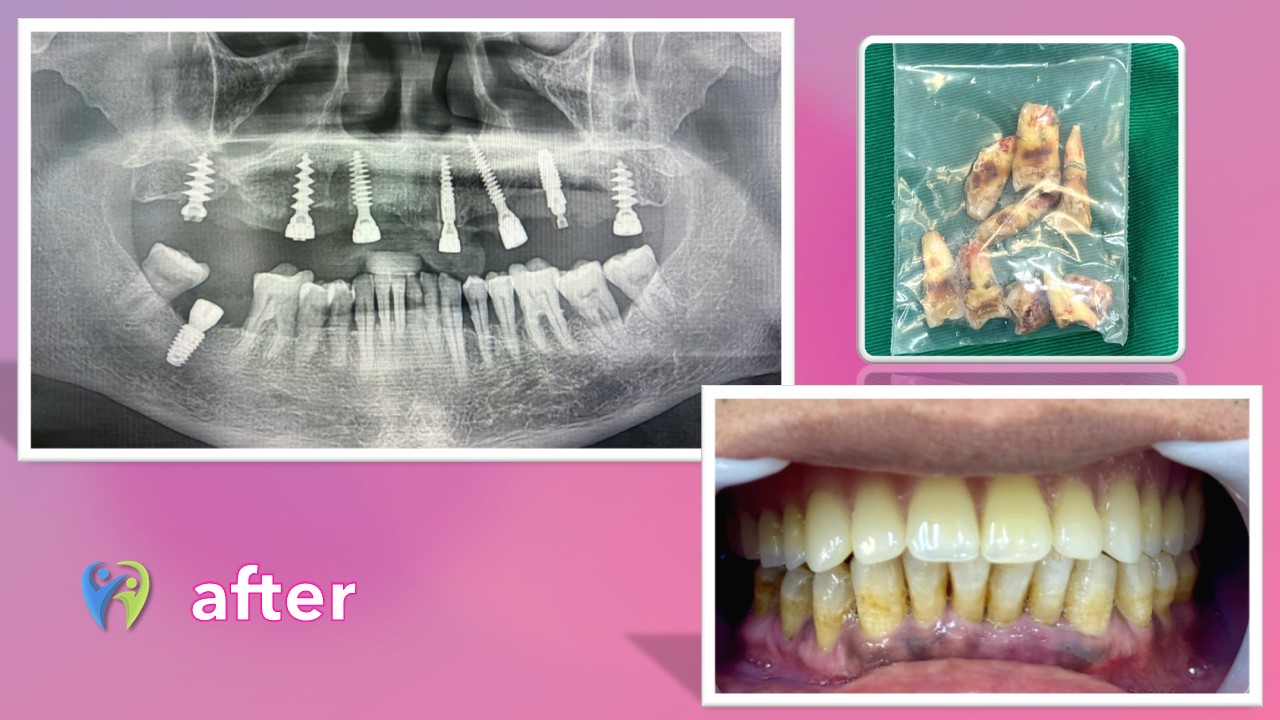

Tại đây, các bác sĩ đã tiến hành thăm khám toàn diện và chụp X-quang Cone Beam CT 3D. Kết quả cho thấy tình trạng mất răng và tổn thương xương hàm trên của chú An rất nghiêm trọng, không thể phục hồi bằng các phương pháp thông thường. Sau khi phân tích kỹ lưỡng, bác sĩ đã đưa ra phác đồ điều trị tối ưu: tiểu phẫu loại bỏ toàn bộ 8 răng hàm trên đã sâu và hỏng, sau đó cấy ghép trực tiếp 8 trụ Implant Thụy Sỹ cao cấp vào cùng một lần phẫu thuật. Đây là một ca phẫu thuật phức tạp, đòi hỏi tay nghề bác sĩ phải cực kỳ cao và trang thiết bị phải tối tân để đảm bảo độ chính xác.

“Quá trình phẫu thuật diễn ra một cách nhẹ nhàng và nhanh chóng, đúng như lời cam kết ban đầu của các bác sĩ. Nhờ vào việc gây tê cục bộ bằng kỹ thuật tiên tiến, tôi không cảm thấy bất kỳ cơn đau hay khó chịu nào trong suốt quá trình. Sau khi nhổ bỏ những chiếc răng đã hỏng, các bác sĩ đã khéo léo và chính xác cấy 8 trụ Implant vào đúng vị trí đã được tính toán từ trước. Các trụ Implant Thụy Sỹ được chọn lựa kỹ càng, đảm bảo chất lượng và khả năng tích hợp xương tốt nhất. Sau đó, một bộ răng tạm đã được lắp đặt ngay lập tức để phục hồi chức năng ăn nhai và thẩm mỹ ngay sau phẫu thuật. Toàn bộ quy trình diễn ra trong môi trường vô trùng sạch sẽ và an toàn. Sau ca phẫu thuật, bác sĩ tiến hành chụp X-quang để thấy sự thành công của quy trình, qua ảnh chụp có 8 trụ Implant được cấy ghép vững chắc, thẳng hàng, tạo thành một nền tảng vững chắc cho hàm răng mới.